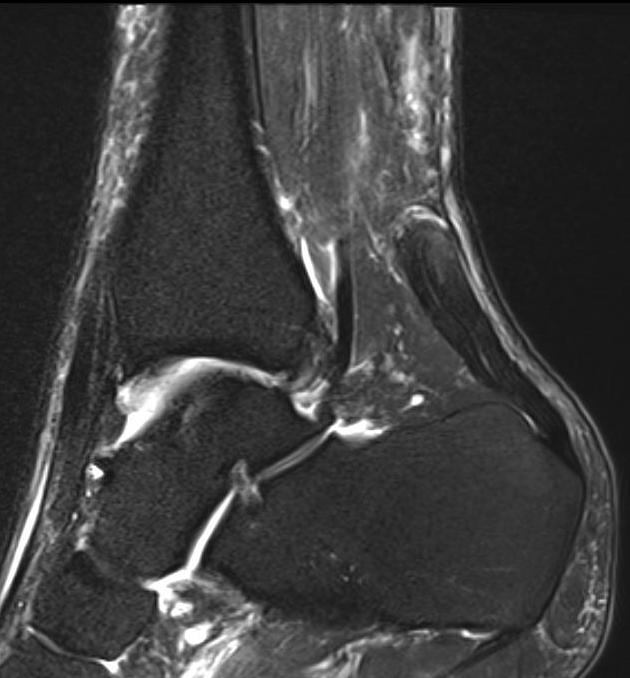

MRI

Indication

- incomplete rupture / clinical uncertainty

- chronic tears - measurement of gap for reconstruction planning

Acute

High grade partial thickness

Chronic retracted

Rerupture

New incomplete tear seen on MRI

Rerupture with scar tissue between tendon ends